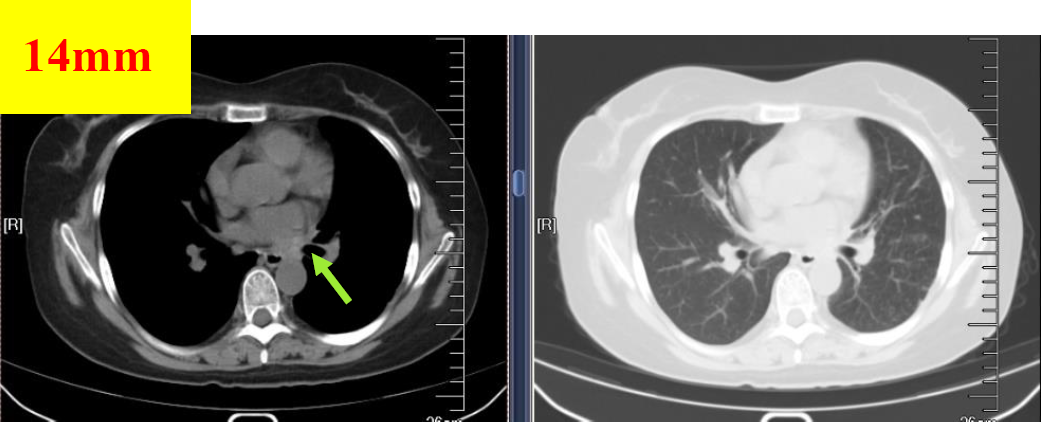

图7 2019.01.06影像学检查(PR)

图8 2019.02.14影像学检查(PR)